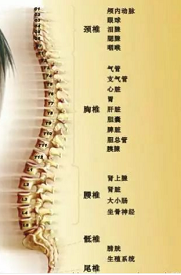

大多数疾病都与我们的骨骼有关,骨骼的好坏强弱是因,疾病是果。

有些父母一直被孩子的身高发育问题困扰,看到孩子比其他同龄人矮一些,担心以后会出现长不高。